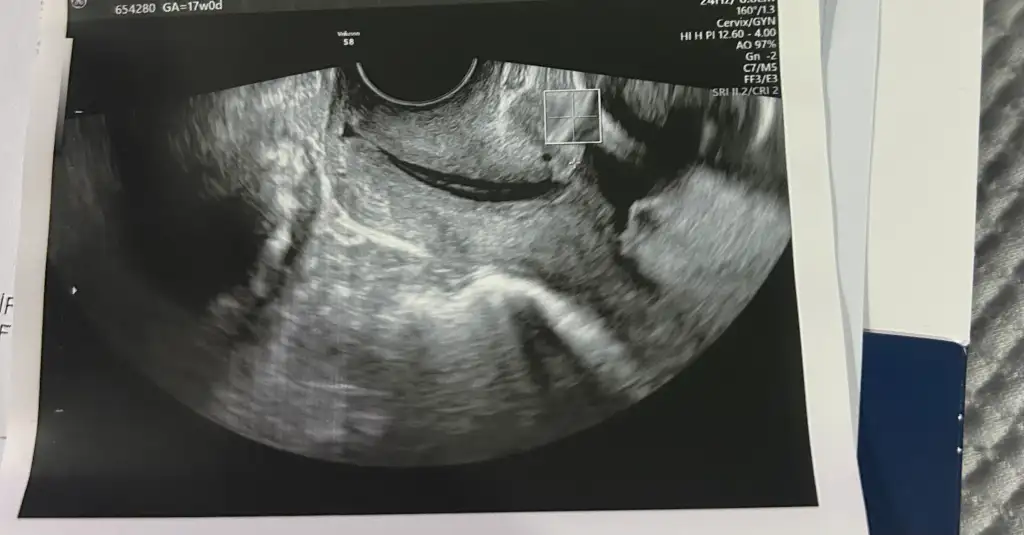

Yani haftan küçük ama ben yine de öyle cok aktif olunmamasindan yanayim. Sonucta bu dikisin amaci aşağı baskıyı azaltmak kalkip yurudukce is güç yaptikca oraya olan baski artar ve dikisler zorlanir. Ben kendi fikrimce cok fazla ayakta gezip dolasmayi is yapmayi dogru bulmuyorum. Tabiki herkes istedigi gibi davranabilir

Özellikle yere çömelme falan yapma. Ve uzun süre ayakta kalma sen yine de. Dikkat et canım.